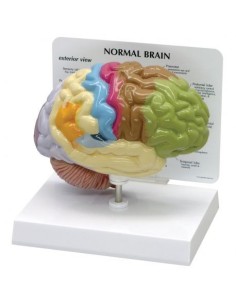

Découvrez le monde de l'anatomie avec des modèles anatomiques de précision

Bienvenue sur Tuttoanatomia.it, le portail de référence en Italie pour l'achat de modèles anatomiques, de posters, de lits portables, de simulateurs médicaux et de littérature spécialisée. Grâce à nos modèles anatomiques de pointe de 3B Scientific et Erler Zimmer, nous offrons une expérience d'apprentissage inégalée.

Des modèles anatomiques détaillés pour tous les besoins

Du crâne en 22 parties à verrouillage magnétique aux modèles de colonne vertébrale, des modèles d'articulation aux modèles de cœur, chaque pièce de notre collection est conçue pour une immersion totale dans l'étude de l'anatomie humaine. Nos modèles, réalisés à partir de scans d'os réels, garantissent une expérience tactile authentique et une fidélité de poids presque identique aux originaux.

Indispensables aux étudiants comme aux professionnels, nos modèles anatomiques sont des outils pédagogiques qui permettent d'observer les structures anatomiques avec précision, en évitant les dissections ou les études invasives. Ils sont également utiles pour expliquer les pathologies aux patients, ce qui rend la communication plus efficace et permet de gagner un temps précieux.